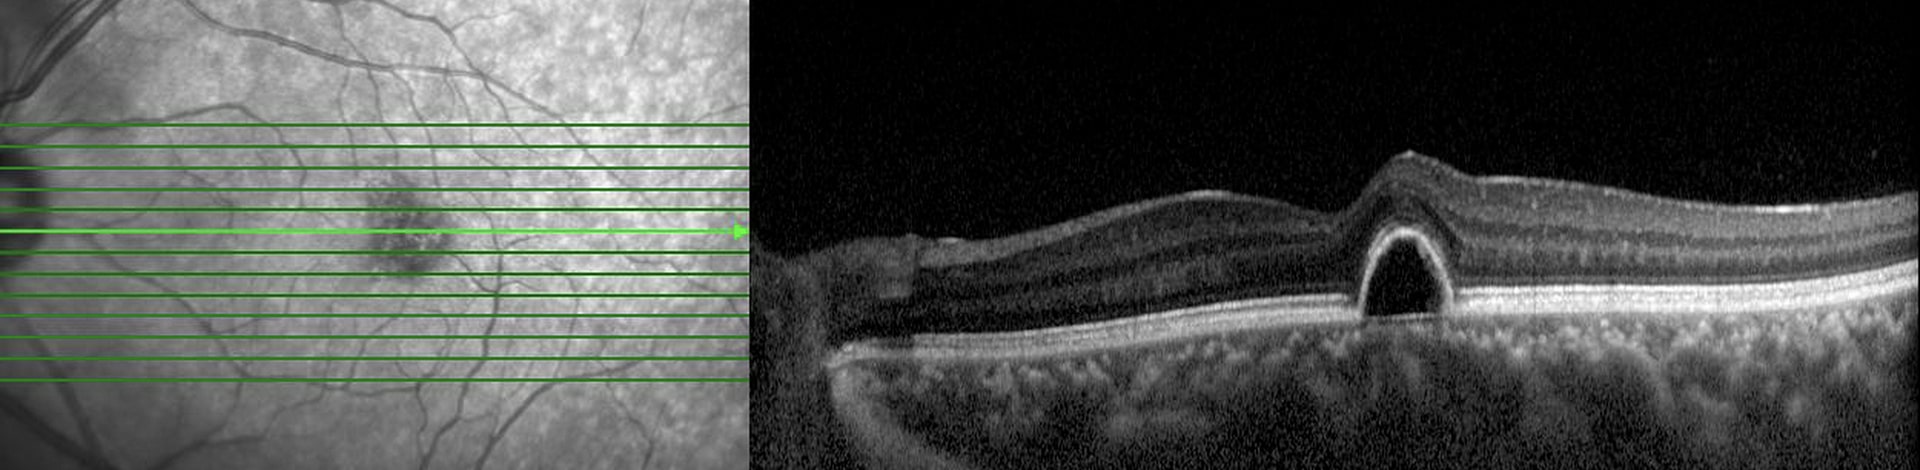

OCT

Optical Coherence Tomography (OCT) is an advanced imaging technology used in medicine to obtain high-resolution, cross-sectional images of biological tissues. It employs light waves to capture detailed images of the eye, specifically the retina, allowing for precise analysis of its layers and structures. This non-invasive imaging technique is instrumental in diagnosing various eye conditions and monitoring changes in eye health over time.

2. High Precision Imaging: It provides highly detailed, three-dimensional images, allowing eye care professionals to visualise subtle changes in the retina and identify abnormalities.